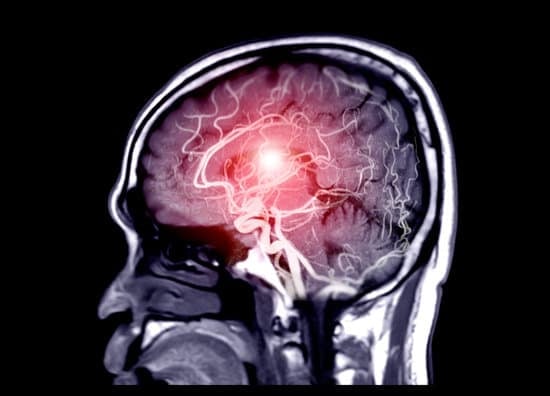

MRA (Magnetic Resonance Angiography): 자기공명 혈관조영술

MRA는 Magnetic Resonance Angiography의 약자로, 자기공명 혈관조영술을 의미합니다.

MRA는 자기공명영상(MRI) 기술을 이용해 혈관 상태를 비침습적으로 촬영하는 검사입니다. 주로 뇌혈관, 심장혈관, 복부 혈관 등 동맥과 정맥의 이상 여부를 확인하는 데 사용됩니다.

뇌혈관질환: 뇌졸중, 동맥류, 혈관 협착 등의 뇌혈관 이상을 진단하는 데 사용됩니다.